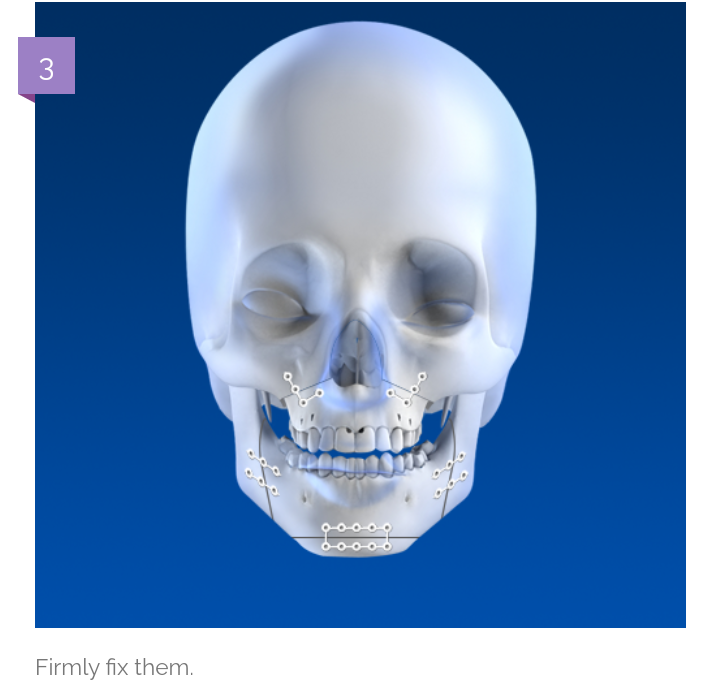

But how its possible to cut centre of maxilla?

Its because of stuff they use to perform surgery

Ultrasonic bone scalpel is great because only affect bone tissues. Make it safer.

How the surgery look?

Shorter nose and Reversed most of the downward growth

And that all possible due to unique scalpel and technique.

But how its possible to cut centre of maxilla?

Its because of stuff they use to perform surgery

Ultrasonic bone scalpel is great because only affect bone tissues. Make it safer.

How the surgery look?

Shorter nose and Reversed most of the downward growth

And that all possible due to unique scalpel and technique.